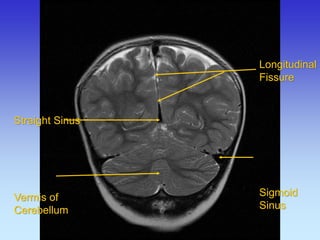

Longitudinal Fissure

Longitudinal

Fissure

Sigmoid

Sinus

Straight Sinus Vermis of Cerebellum

Straight Sinus

Transverse Sinus

Superior Sagittal Straight Sinus

Cerebellum

Superior Sagittal Sinus

Occipital Lobe